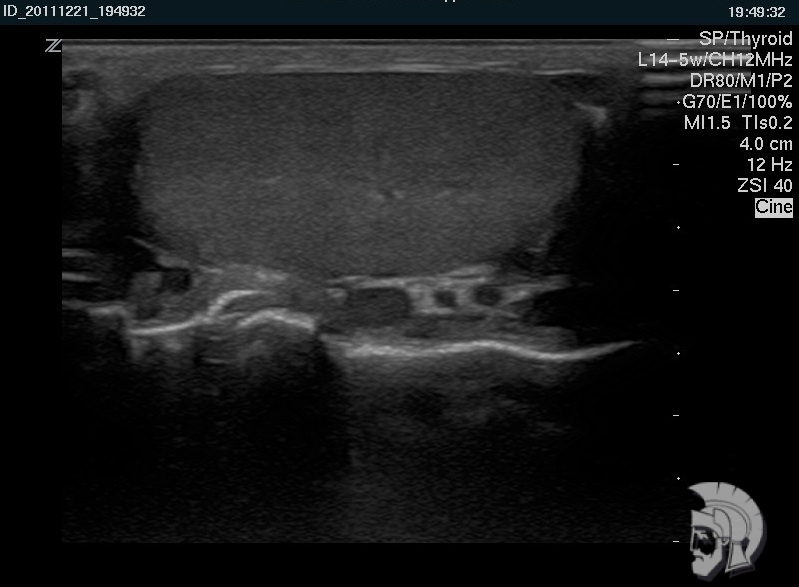

Резкая боль в паху заставила обратиться к врачу. После диагностики на специальном аппарате УЗИ было назначено скорое лечение. Спасибо за быструю диагностику и лечение! Очень тактичный и профессиональны й персонал! С ув. Михаил Васильевич, г.Пятигорск.